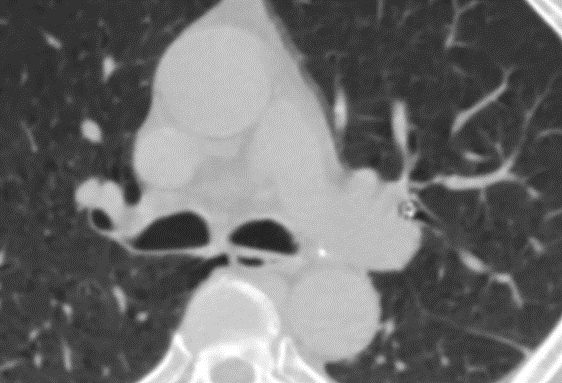

▲术前CT